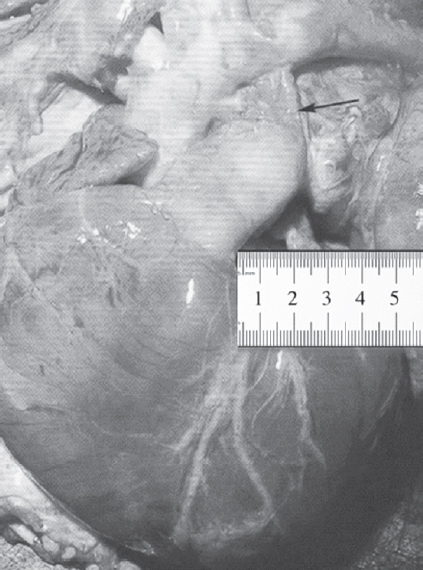

Fetal communication in the vascular system of the fetus is necessary for fetal blood circulation. Metabolic support is provided through the placenta and vessels of the umbilical cord. The function of the arterial duct (ductus arteriosus) is the main component of the fetal blood circulation, which acts as a link between the pulmonary artery and aorta when the baby’s lungs are not functioning and the placenta is the gas exchange organ. Disorders occurring in the physiological processes of the cardiovascular system, especially in the intranatal period, can lead to the development of severe pathology. One of the most important defects in the structure and, consequently, in the nature of the blood flow, is the failure of the arterial duct. The patent ductus arteriosus is a necessary anatomical structure at the heart of the fetal circulatory system. Normally, the patent ductus arteriosus (PDA) must close soon after birth, turning into a ligamentum arteriosum. If there is no closure of the duct or its partial obliteration occurs, then it means there is the presence of the defect. The references to it go far into antiquity. This review presents the main stages of study, anatomical and physiological features of the ductus arteriosus.